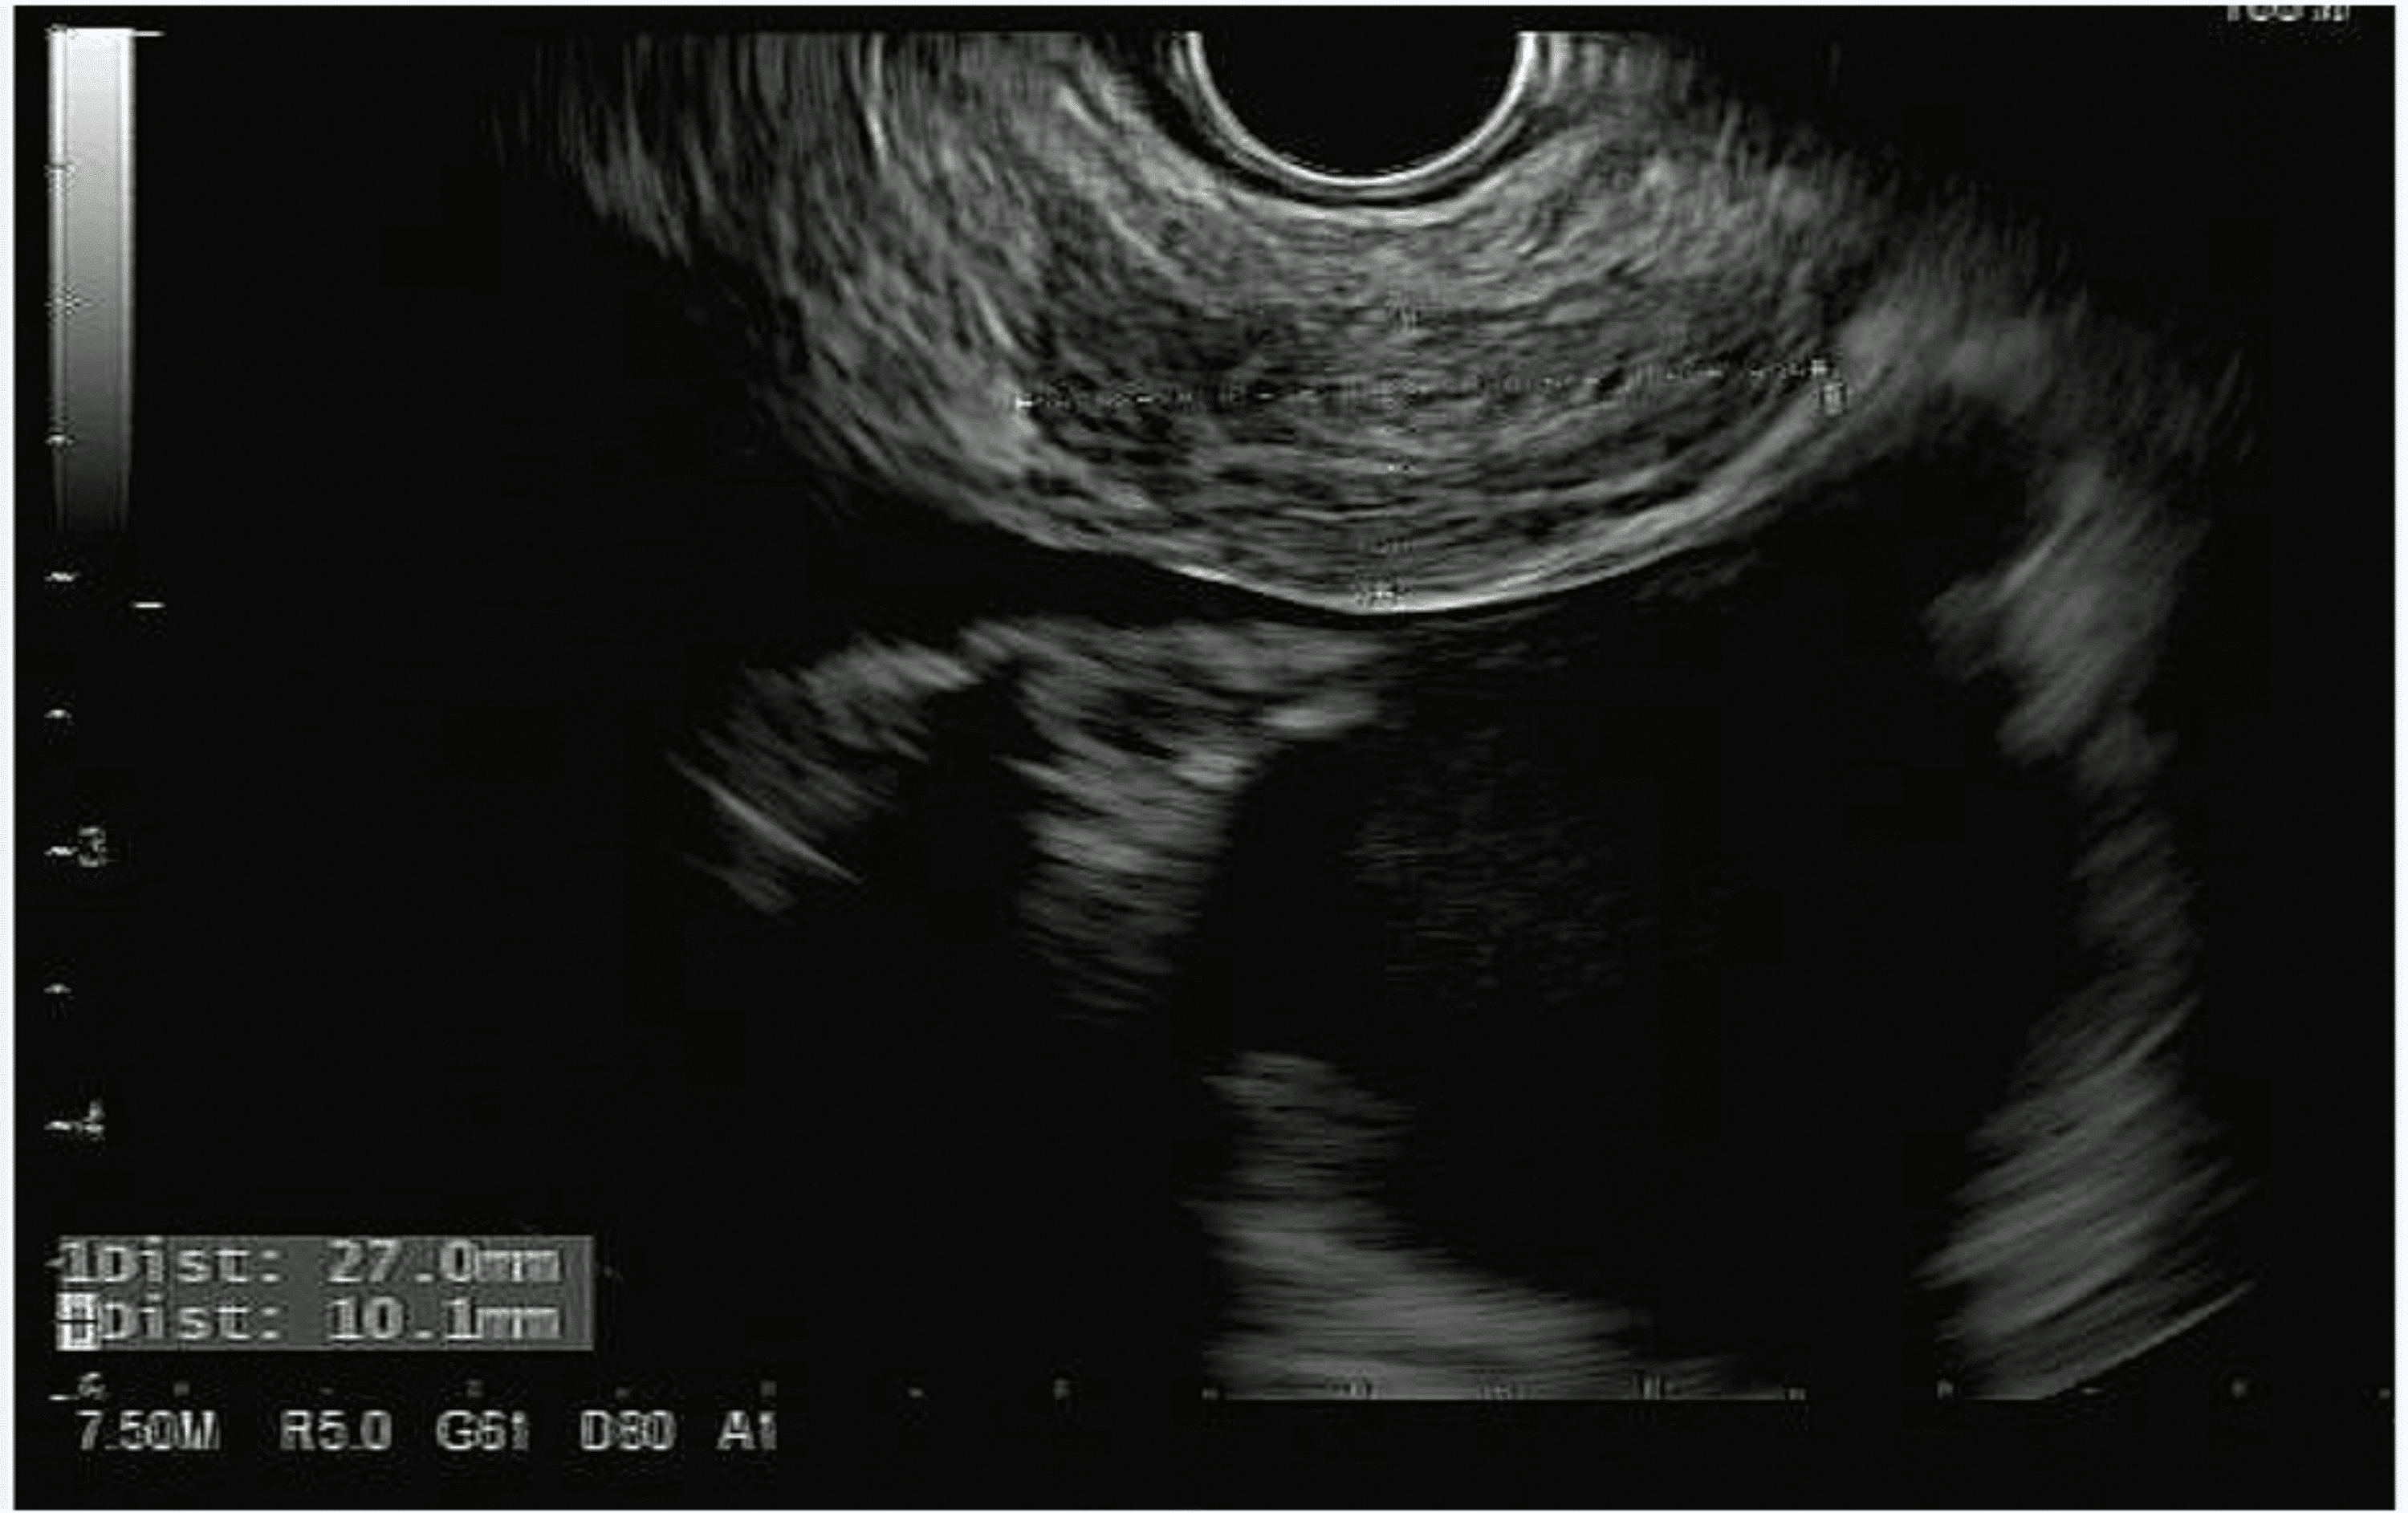

Endoscopic ultrasonography image of the esophagus. The arrow shows a Endoscopic Esophageal Ultrasound An eus uses ultrasound waves to. an endoscopic ultrasound scan (eus) is an internal scan that shows images of the digestive tract. endoscopic ultrasound (eus) is an increasingly available diagnostic and therapeutic tool used within the uk. A small ultrasound probe on. This includes organs such as the stomach, pancreas, and gallbladder, as well as nearby structures and. Endoscopic Esophageal Ultrasound.

Endoscopic ultrasound view of a T1b esophageal cancer. The cancer Endoscopic Esophageal Ultrasound endoscopic ultrasound is a minimally invasive procedure that uses a camera device (endoscope) together with high frequency sound waves (ultrasound) to examine the gi tract and beyond. A regular endoscope is a thin, lighted tube that can be inserted through the mouth or anus to view inside your esophagus, stomach or intestines. endoscopic ultrasonography (eus) has evolved from. Endoscopic Esophageal Ultrasound.

Linear endoscopic ultrasound image depicting mass with loss of wall Endoscopic Esophageal Ultrasound It can look at parts of your upper. endoscopic ultrasound (eus) is a procedure that allows a doctor to obtain images and information about your esophageal and. Endoscopy — use of a scope to look at the. gz endoscopic ultrasound (eus) offers a characterization of benign versus malignant processes. endoscopic ultrasound (eus) is a procedure that uses. Endoscopic Esophageal Ultrasound.

Endoscopic ultrasonography showed a normal esophageal wall and a cystic Endoscopic Esophageal Ultrasound endoscopic ultrasound (eus) is a test that uses a camera and sound waves to produce live images of parts of the digestive system. Eus can be used to. an endoscopic ultrasound, or eus, is a minimally invasive procedure that can be used to diagnose a wide range of. endoscopic ultrasound is a minimally invasive procedure that uses. Endoscopic Esophageal Ultrasound.